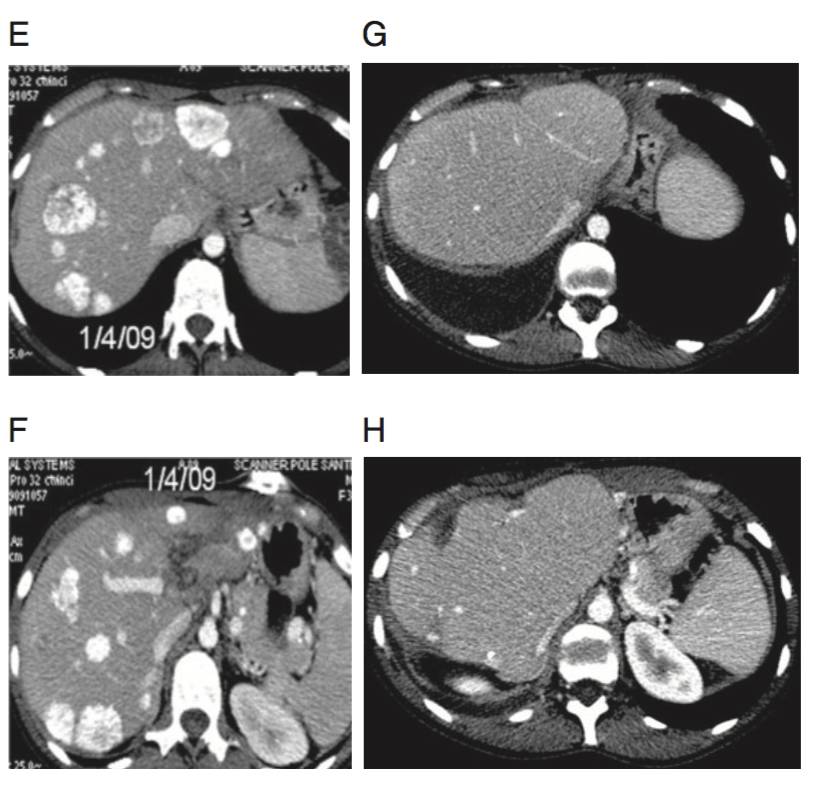

(E&F)4周期三药方案HAI+西妥昔单抗治疗后,复查CT评价为显著影像学缓解。行分期肝切除术。

(G&H)术后3年复查未见肿瘤复发,PS评分=0。